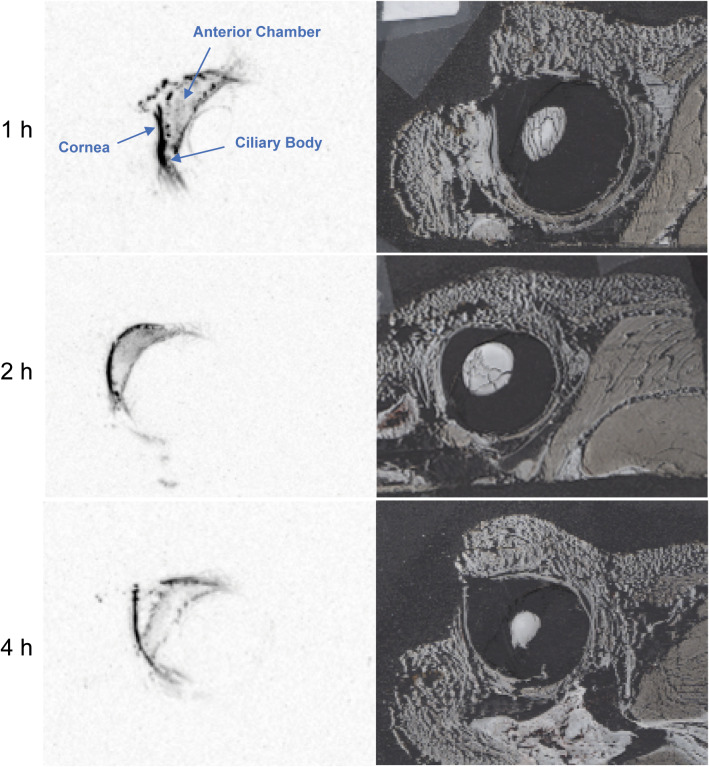

Representative sections and autoradiographs from in situ eyes of animals that received a single intracameral dose of 14C-latanoprost are shown in Fig. 2. Radioactivity was concentrated in ocular tissues including the cornea, iris, ciliary body, and anterior chamber after intracameral dosing. There was a diminution of signal in the anterior segment from 1 to 4 h post intracameral dose. No radioactivity was detected in the eyelids or other periorbital tissues after intracameral dosing.

Fig. 2.

Representative sections of fresh-frozen eyes in situ (right) and corresponding autoradiographs (left) from beagle dogs that received a single bilateral intracameral administration of 14C-latanoprost. Eyes in situ were collected at 1, 2, and 4 h after the administration. Annotations identify tissues and areas of interest